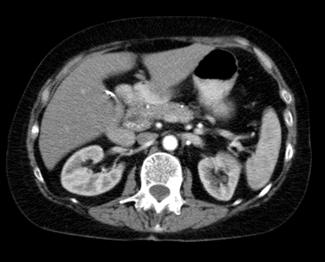

Tomografía: determina la localización

♦ La mayoría de los gastrinomas se encuentran en un área llamada triángulo del gastrinoma. (Ver Figura 58)

♦ Duodeno (70% de los casos)

♦ Páncreas (25% de los casos) → típicamente la cabeza

♦ Ubicaciones ectópicas (5 a 15% de los casos): Hígado, ganglios linfáticos peri pancreáticos, ovarios